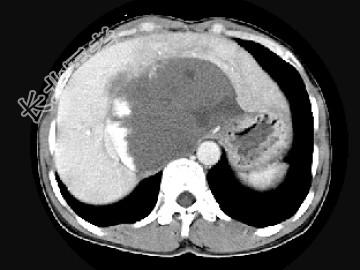

- 单项选择题女,48岁, 中上腹不适,CT扫描如图, 最可能的诊断为 ( )

A、原发性肝癌

B、胆管细胞癌

C、肝血管内皮瘤

D、肝血管瘤

E、小肠间质瘤